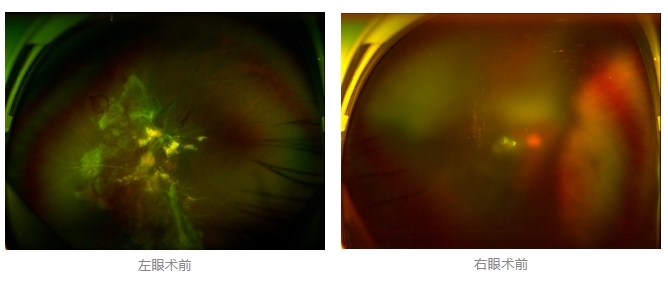

經廈門眼科中心眼底病??菩姓魅瓮鯐圆z查后,確診其雙眼糖尿病視網膜病變VI期,伴發(fā)雙眼視網膜脫離和黃斑水腫,且右眼視網膜上增殖膜叢生,若再不盡快進行治療,恐有失明風險。

面對陳先生的復雜病情,王曉波主任采用玻璃體切割術聯(lián)合膜切除術等方式,精細剝離牽拉視網膜的增殖膜,復位脫離的視網膜,同時進行玻璃體腔注藥促進黃斑水腫吸收。

經過規(guī)范化治療,術后2個月復查時陳先生的視力已有明顯改善,矯正視力從眼前指數(shù)提升至0.3,成功擺脫“失明危機”。但王曉波主任強調:“這只是階段性勝利,后續(xù)治療不能松懈。”